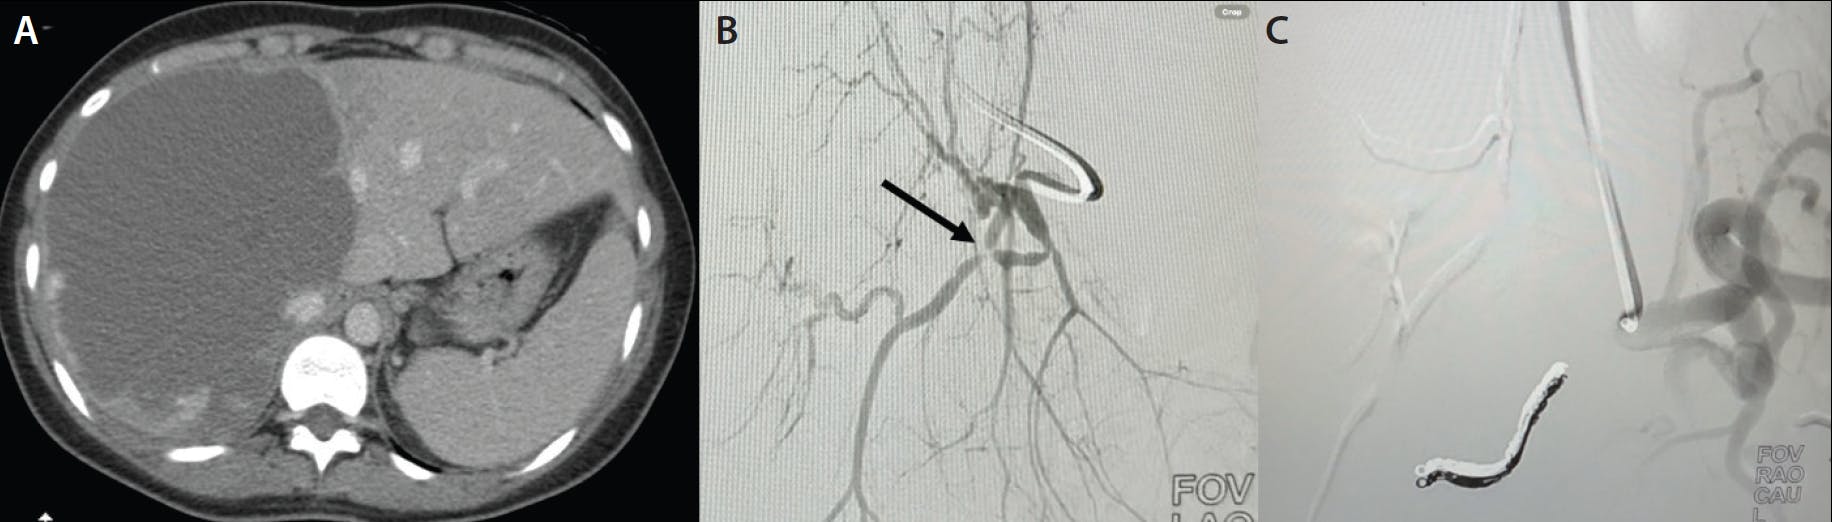

A woman in her early 60s with cholangiocarcinoma presented with external brisk bleeding through the left percutaneous transhepatic biliary drain skin tract during internal-external biliary tube exchange. Hepatic vascular injury was suspected. A celiac angiogram showed a distal left hepatic artery pseudoaneurysm (Figure 2A). A 0.016-inch Glidewire GT-R microwire was used for superselective microcatheterization in very tortuous anatomy, and a “front door-back door” coil embolization technique was used to treat the vascular injury effectively, utilizing a 0.018-inch, 3mm X 8cm AZUR™ CX coil for backstop and a 20-cm AZUR HydroPack™ coil (both Terumo Interventional Systems) (Figure 2B-D).

Figure 2. Celiac angiogram showing the distal left hepatic artery pseudoaneurysm (arrow) (A). Superselective microcatheterization with the 0.016-inch Glidewire GT-R microwire in very tortuous anatomy and a “front door-back door” coil embolization used to treat the vascular injury (B-D).